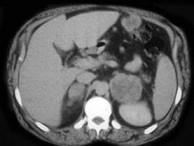

问题 男,56岁,有恶性黑色素瘤病史,请结合图像,作出诊断()

选项 A.肾上腺腺瘤 B.肾上腺髓样脂肪瘤 C.肾上腺癌 D.肾上腺转移瘤 E.肾上腺嗜铬细胞瘤

答案 D